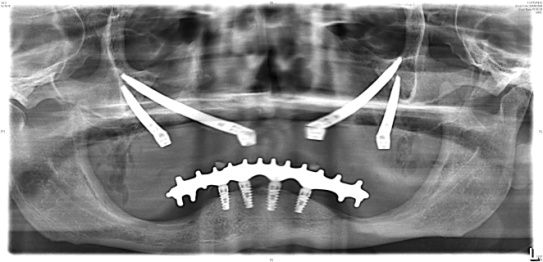

Chirurgia Oro-Mascellare per riabilitazioni protesiche post oncologiche

I pazienti che per motivi oncologici o per esito di osteonecrosi per uso di farmaci della categoria bifosfonati (in uso nelle gravi forme di osteoporosi o nel trattamento coadiuvante delle metastasi ossee)hanno subito gravi demolizioni dei mascellari e conseguente perdita della funzionalità masticatoria necessitano di ricostruzione e rifunzionalizzazione dell'apparato masticatorio con ricostruzione dell'osso mandibolare o del mascellare superiore attraverso innesti di osso , di lembi mucosi e/o muscolari di vicinanza ed a volte di implantologia preprotesica con impianti zigomatici , pterigoidei o convenzionali , tutto cio'con il fine di ripristinare una corretta funzione ma anche una auspicabile vita di relazione.